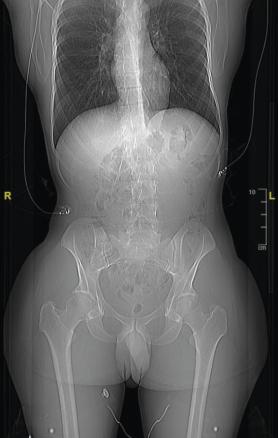

• Il mesure 1,91 m et pèse 92 kg. L’examen révèle une cyphose et une scoliose (fig. 1). Un prognathisme, une macroglossie, une hypertrophie des golfes frontaux, un élargissement des mains (fig. 2) et des pieds (il chausse du 47) ainsi que des sueurs nocturnes sont également constatés.